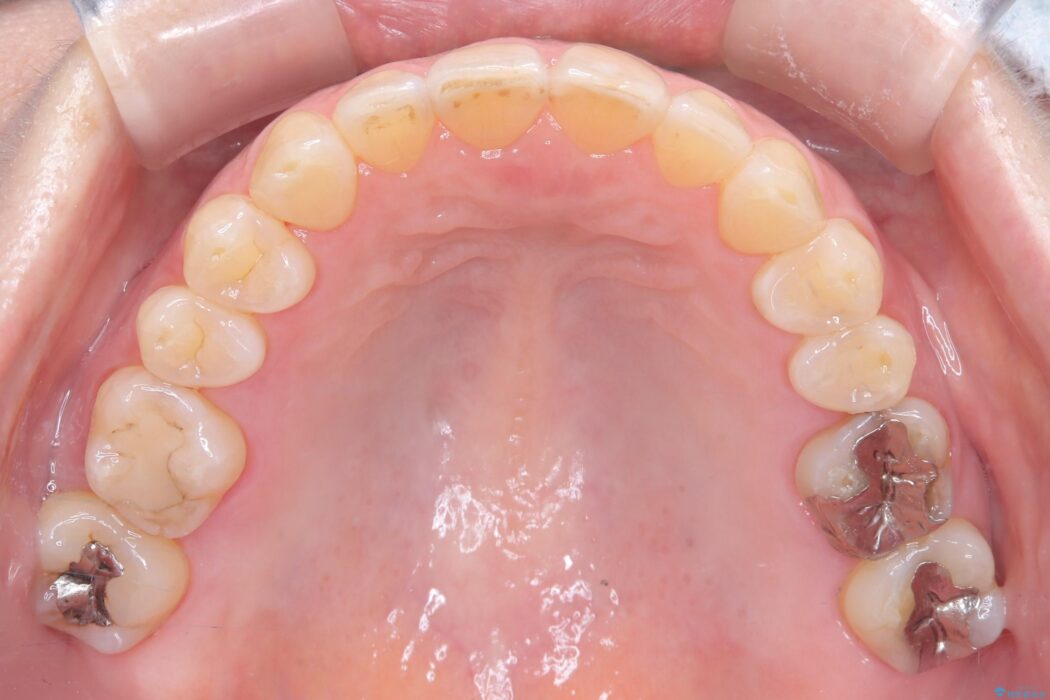

今回の矯正治療では、歯の色に近い目立たない審美ブラケットとワイヤーを使用しました。

ワイヤー矯正ならではの確実な歯のコントロールにより、当初の計画通り約1年という短い期間で、前歯のガタつきが解消。見た目が美しく整っただけでなく、清掃しやすい機能的な歯並びを獲得していただけました。